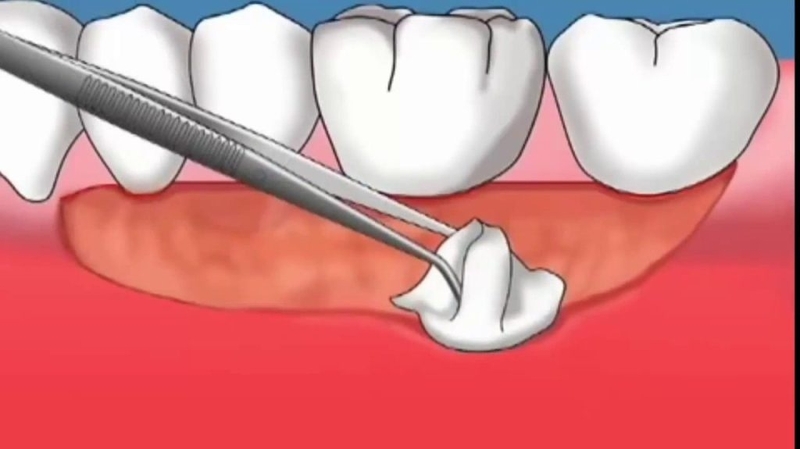

Trong trường hợp tụt nướu nhẹ, bạn chỉ cần làm sạch sâu vị trí chân răng. Bác sĩ sẽ loại bỏ các mảng bám và cao răng dưới nướu. Sau đó, dùng các dụng cụ chuyên dụng làm trơn và mượt bề mặt chân răng, giúp lợi bám chặt hơn vào răng.

Nếu lợi đã bị tụt quá sâu và chân răng lộ nhiều, bác sĩ sẽ chỉ định phẫu thuật ghép lợi. Bệnh nhân có thể được tiến hành ghép lợi tự thân hoặc ghép tổ chức liên kết biểu mô để che đi phần chân răng lộ ra. Nhờ đó, răng sẽ vững chắc hơn trên nướu, ngăn chặn tình trạng bệnh trở nên trầm trọng hơn.